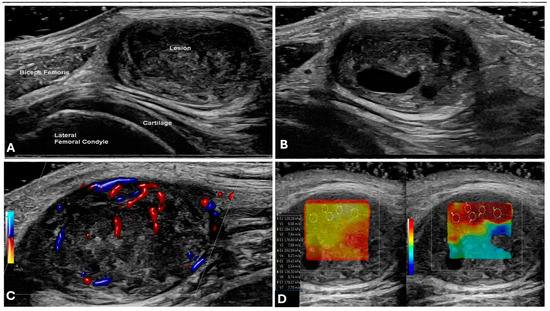

- Primary Sarcomas: Soft-tissue sarcomas are uncommon, accounting for just over 1% of adult malignancies. Synovial sarcoma, clear cell sarcoma, and epithelioid sarcomas are known to involve peripheral nerves. CT/MR reveals a large soft tissue mass with areas of necrosis or calcification and heterogeneous contrast enhancement. F-18 FDG uptake is useful for both tumor staging and treatment assessment (Figure 26, Figure 27 and Figure 28).